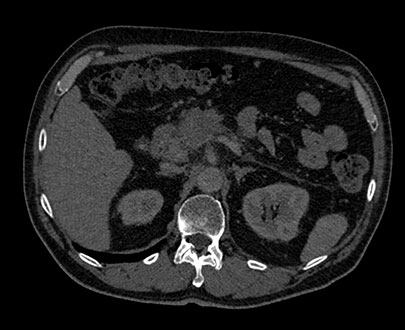

Выбирайте значение уровня энергии от 45 до 125 кВп, чтобы просмотреть структуры в соответствии с их характеристиками спектрального затухания.

В режиме MonoE показаны синтезированные моноэнергетические изображения с предустановленными значениями кВп в диапазоне от 40 до 200 кВп. При изменении значения кВп также происходят изменения на изображении, даже при сохранении настроек окна/уровня. Например, при более низком значении кВп йод может проявляться ярче, а при более высоком значении количество артефактов от металлических объектов может быть снижено.